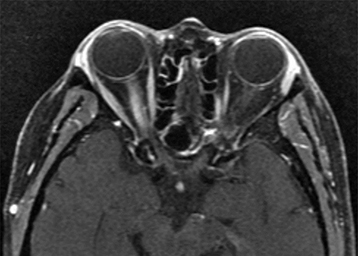

For all cases, MRI of the brain and orbits with gadolinium and fat suppression should be obtained (See Figures 10.14.1 and 10.14.2). While a short segment of optic nerve is involved in typical optic neuritis, lesions in NMOSD may be longitudinally extensive. In addition, patients with NMOSD should have MRI of the spine to look for signs of transverse myelitis. Antibodies for anti-aquaporin 4 (anti-AQP4) and anti-myelin oligodendrocyte glycoprotein (anti-MOG) should be drawn.